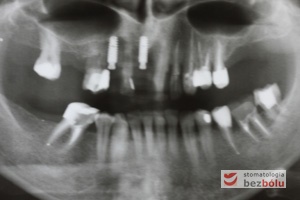

Diagnostyka radiologiczna - ortopantomogram wskazuje zęby nierokujące do usunięcia i liczne wypełnienia do wymiany

Diagnostyka radiologiczna – ortopantomogram wskazuje zęby nierokujące do usunięcia i liczne wypełnienia do wymiany